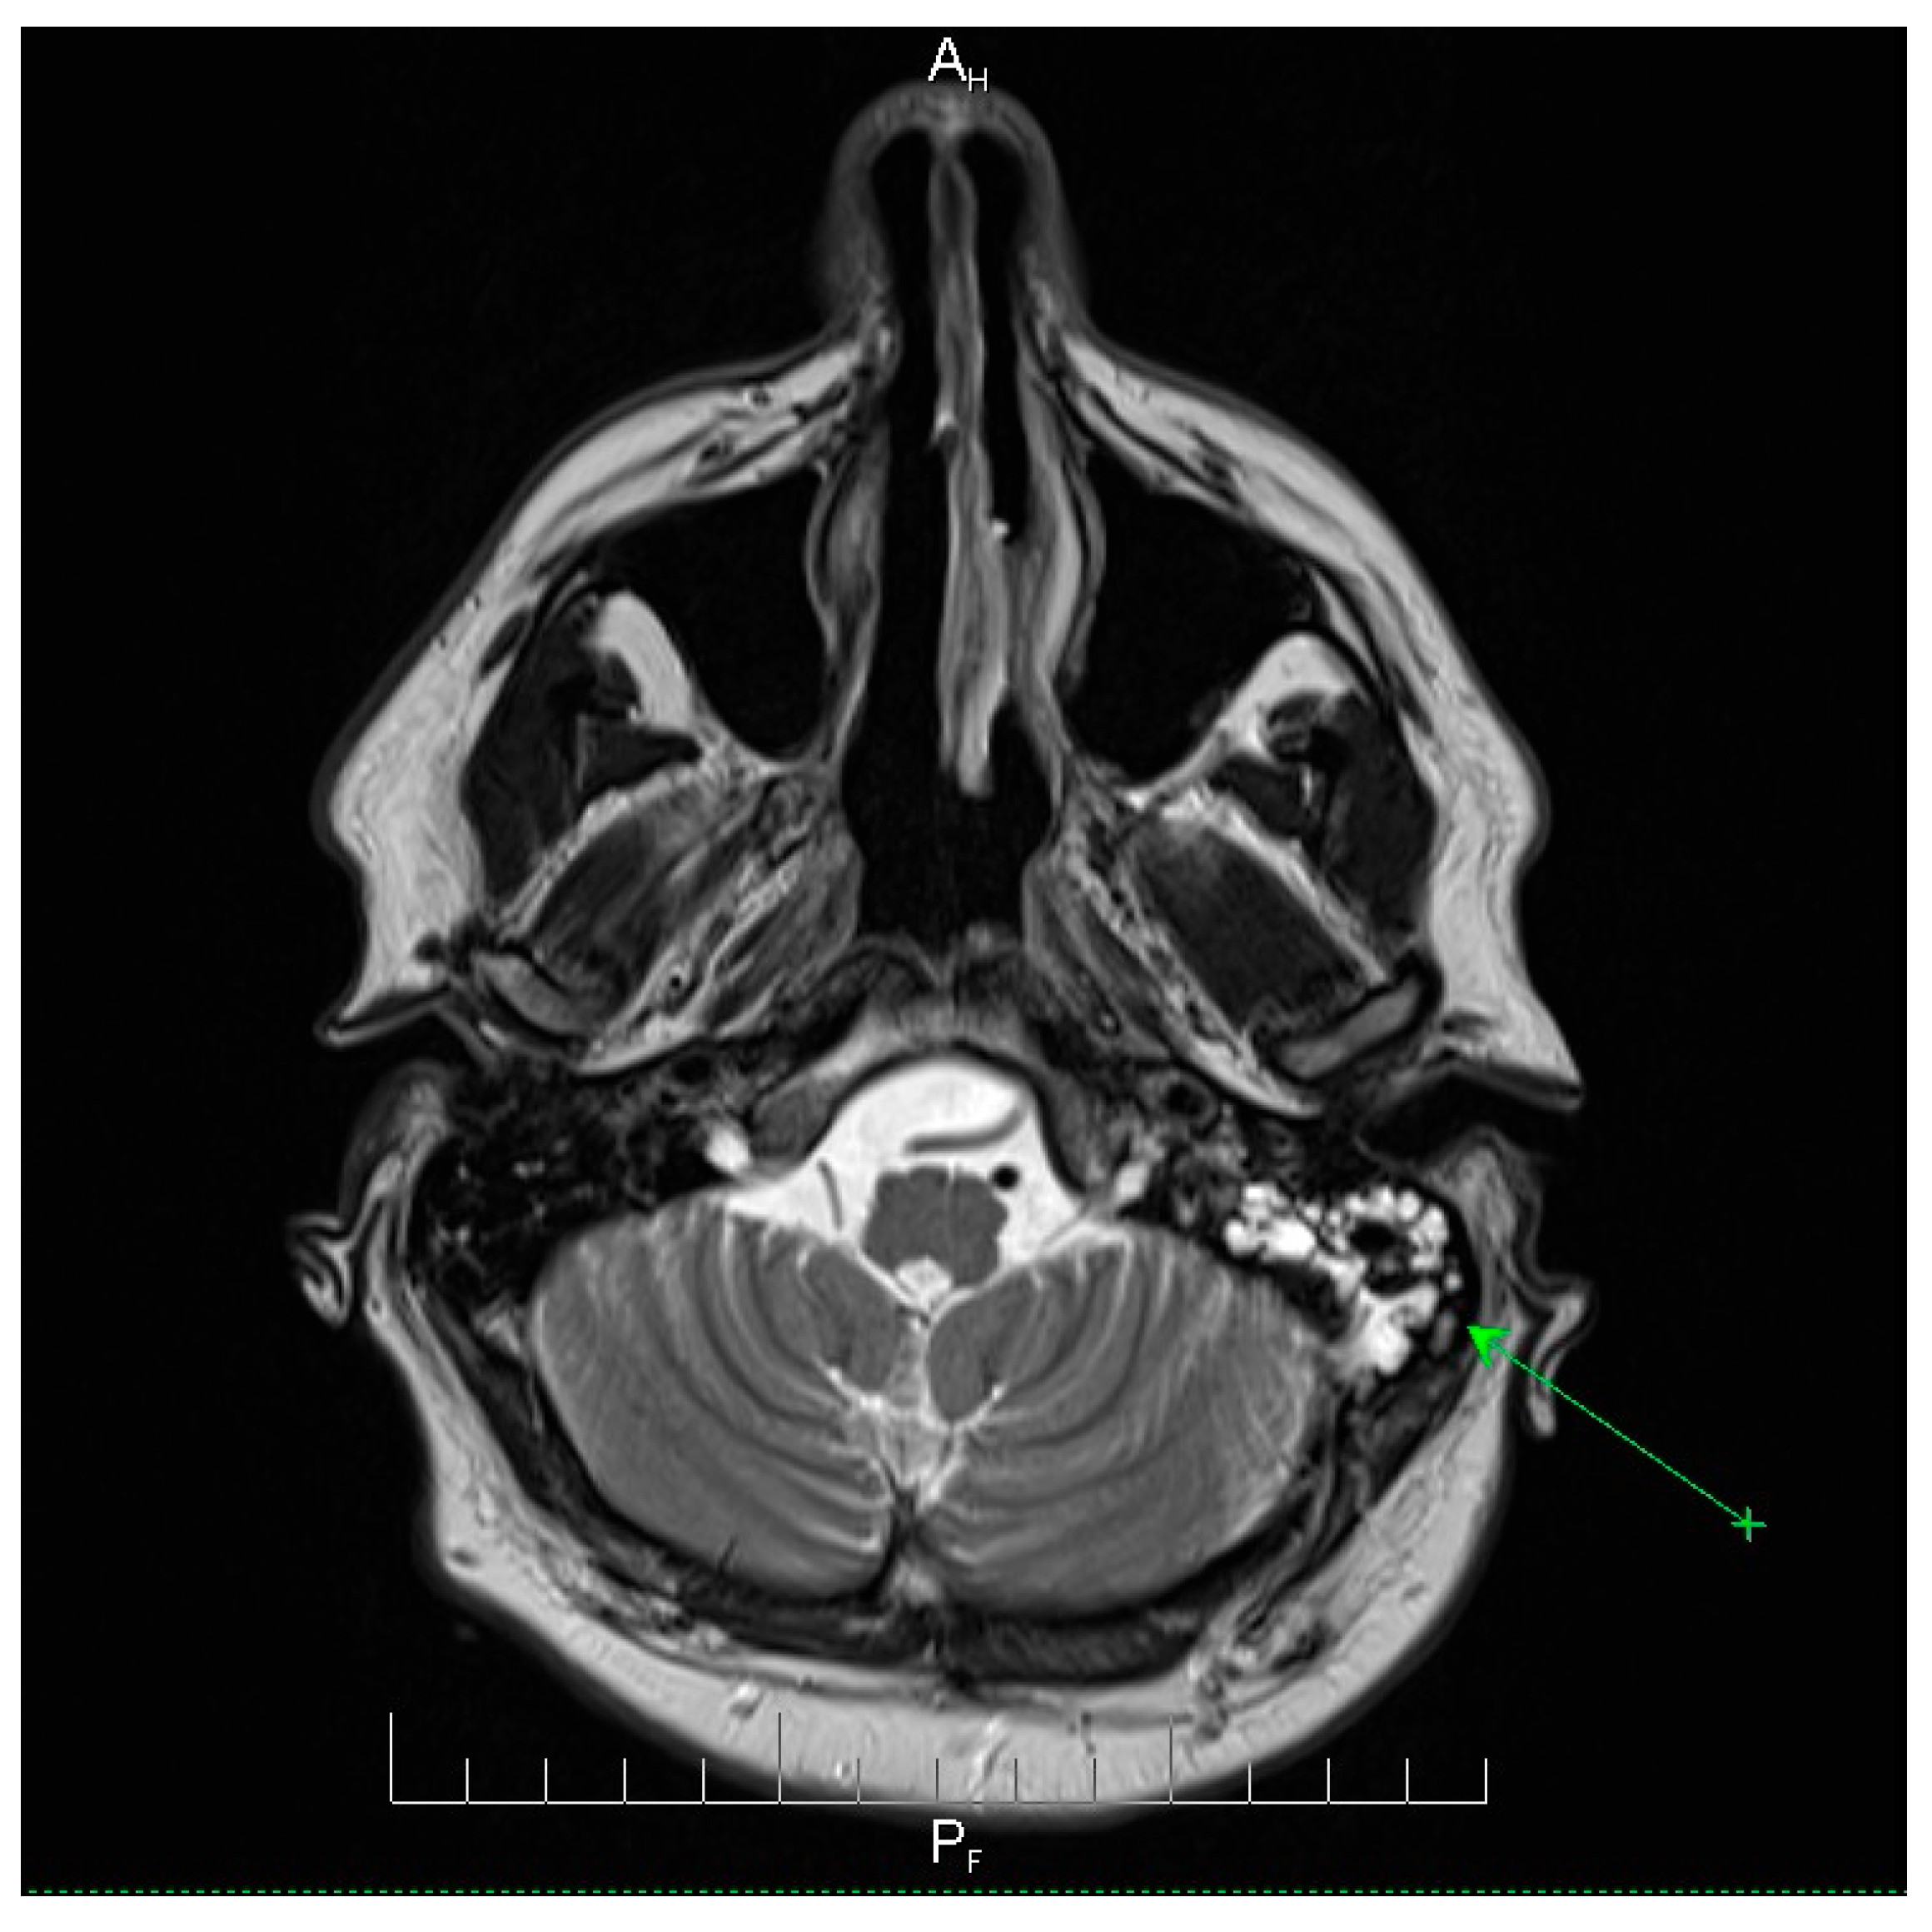

Neuroimaging revealed mild ethmoidal/sphenoidal sinus opacification and left mastoid air cell involvement without evidence of parenchymal lesions or venous sinus thrombosis (Figure 1, Figure 2 and Figure 3). Coronal and axial T2-weighted MRI sequences revealed para-fluid collections within the left mastoid air cells extending toward Citelli’s angle (Figure 1, Figure 2 and Figure 3), consistent with an otogenic focus and a possible contiguous route for intracranial spread.

Figure 1.

Coronal T2-weighted MRI scan demonstrating para-fluid collections within the left mastoid air cells extending toward Citelli’s angle (green arrow). There was no evidence of parenchymal lesions, intracerebral edema, or venous sinus thrombosis. The surrounding brain parenchyma and the ventricular system appeared normal. These findings are consistent with localized mastoid involvement and help exclude intracranial complications, providing an important radiological context for the patient’s clinical presentation. Hp = head-posterior (shows the orientation of image). FA = foot-anterior (indicates the directional axis at the bottom of the image).